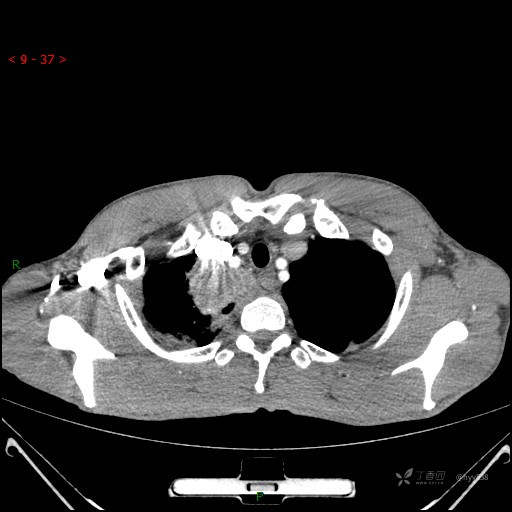

增强动脉期